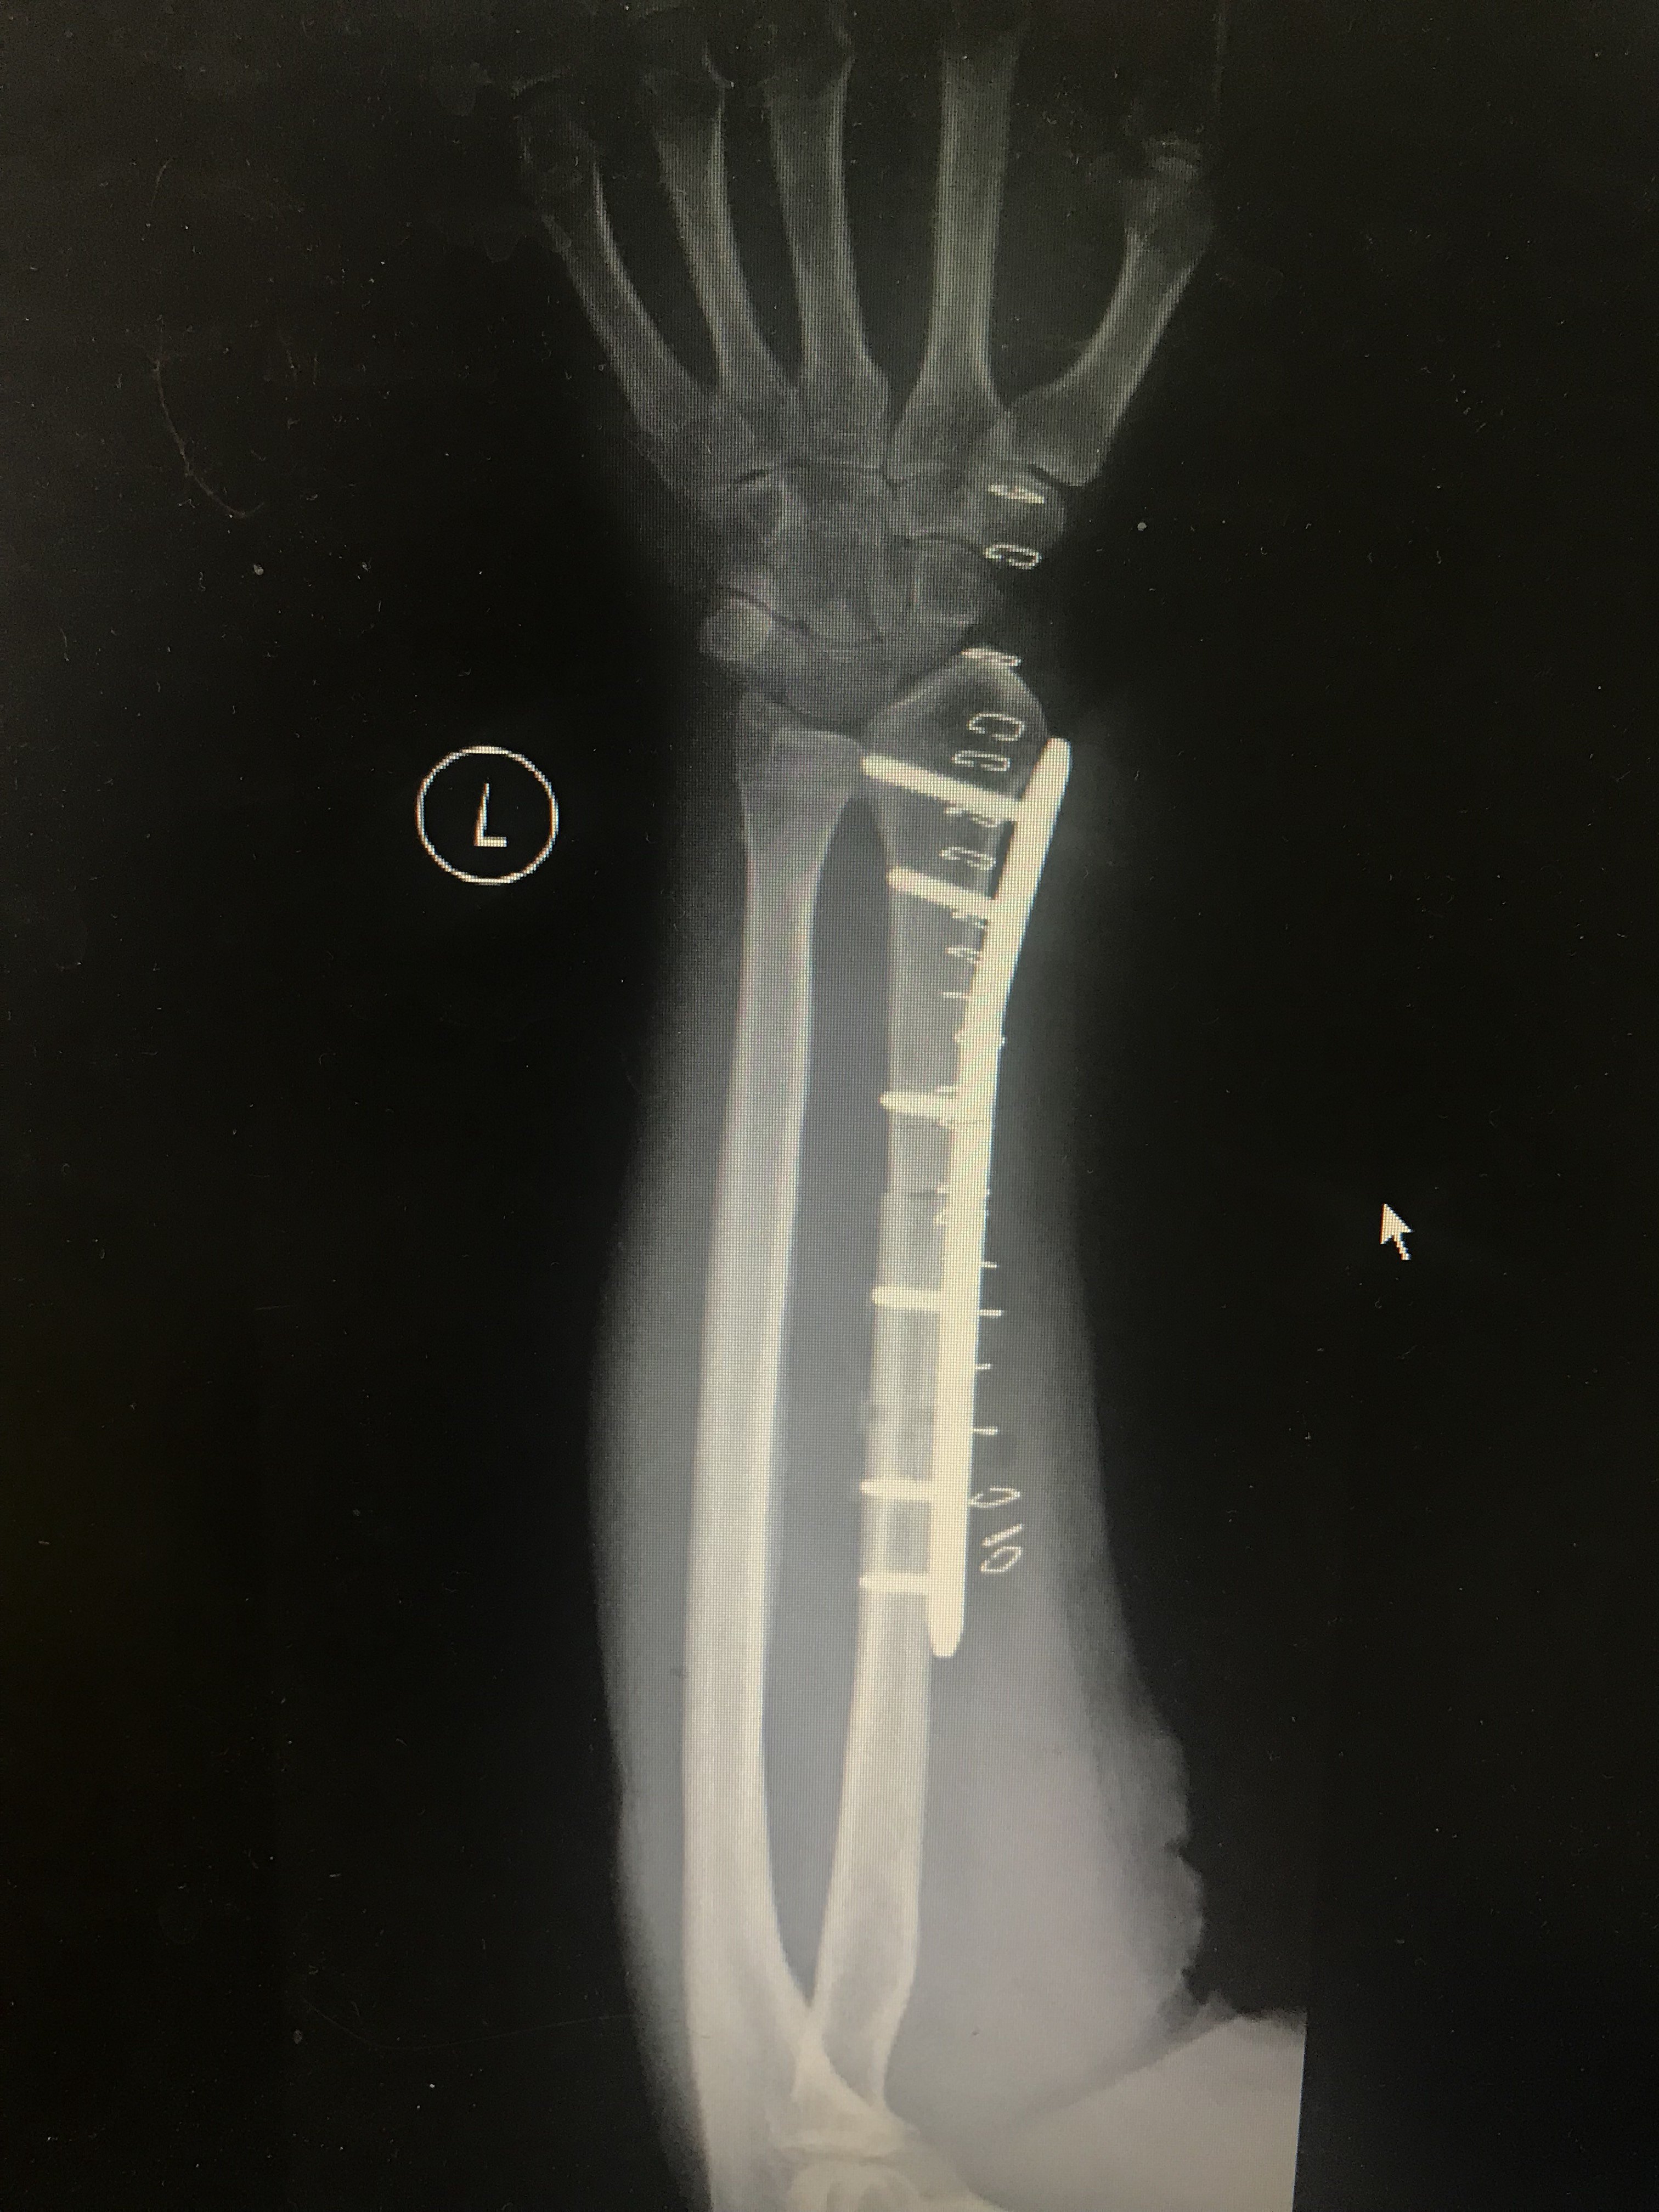

桡骨骨巨细胞瘤多次手术后桡骨缺损,腕关节畸形,行腕关节融合术 - 抖